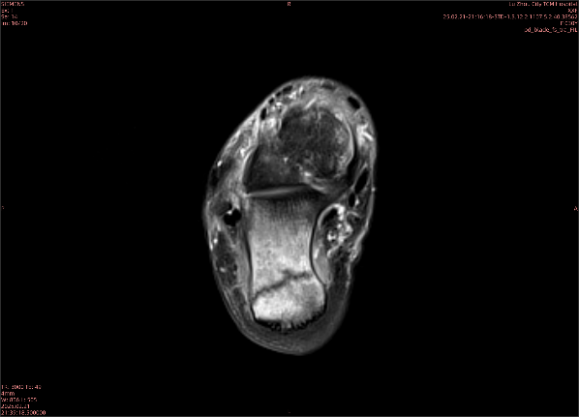

舉例圖像

圖2

專業(yè)解釋看不懂沒關(guān)系,大家看圖1和圖2就可以了,這是同一個(gè)患者跟骨的磁共振和CT圖像,圖1的紅色箭頭指示的黑線就是磁共振圖像顯示的骨折線,一目了然。而對比圖2的CT圖像上并未顯示異常。

這下大家明白了吧,如果懷疑隱匿性骨折優(yōu)先選擇磁共振檢查